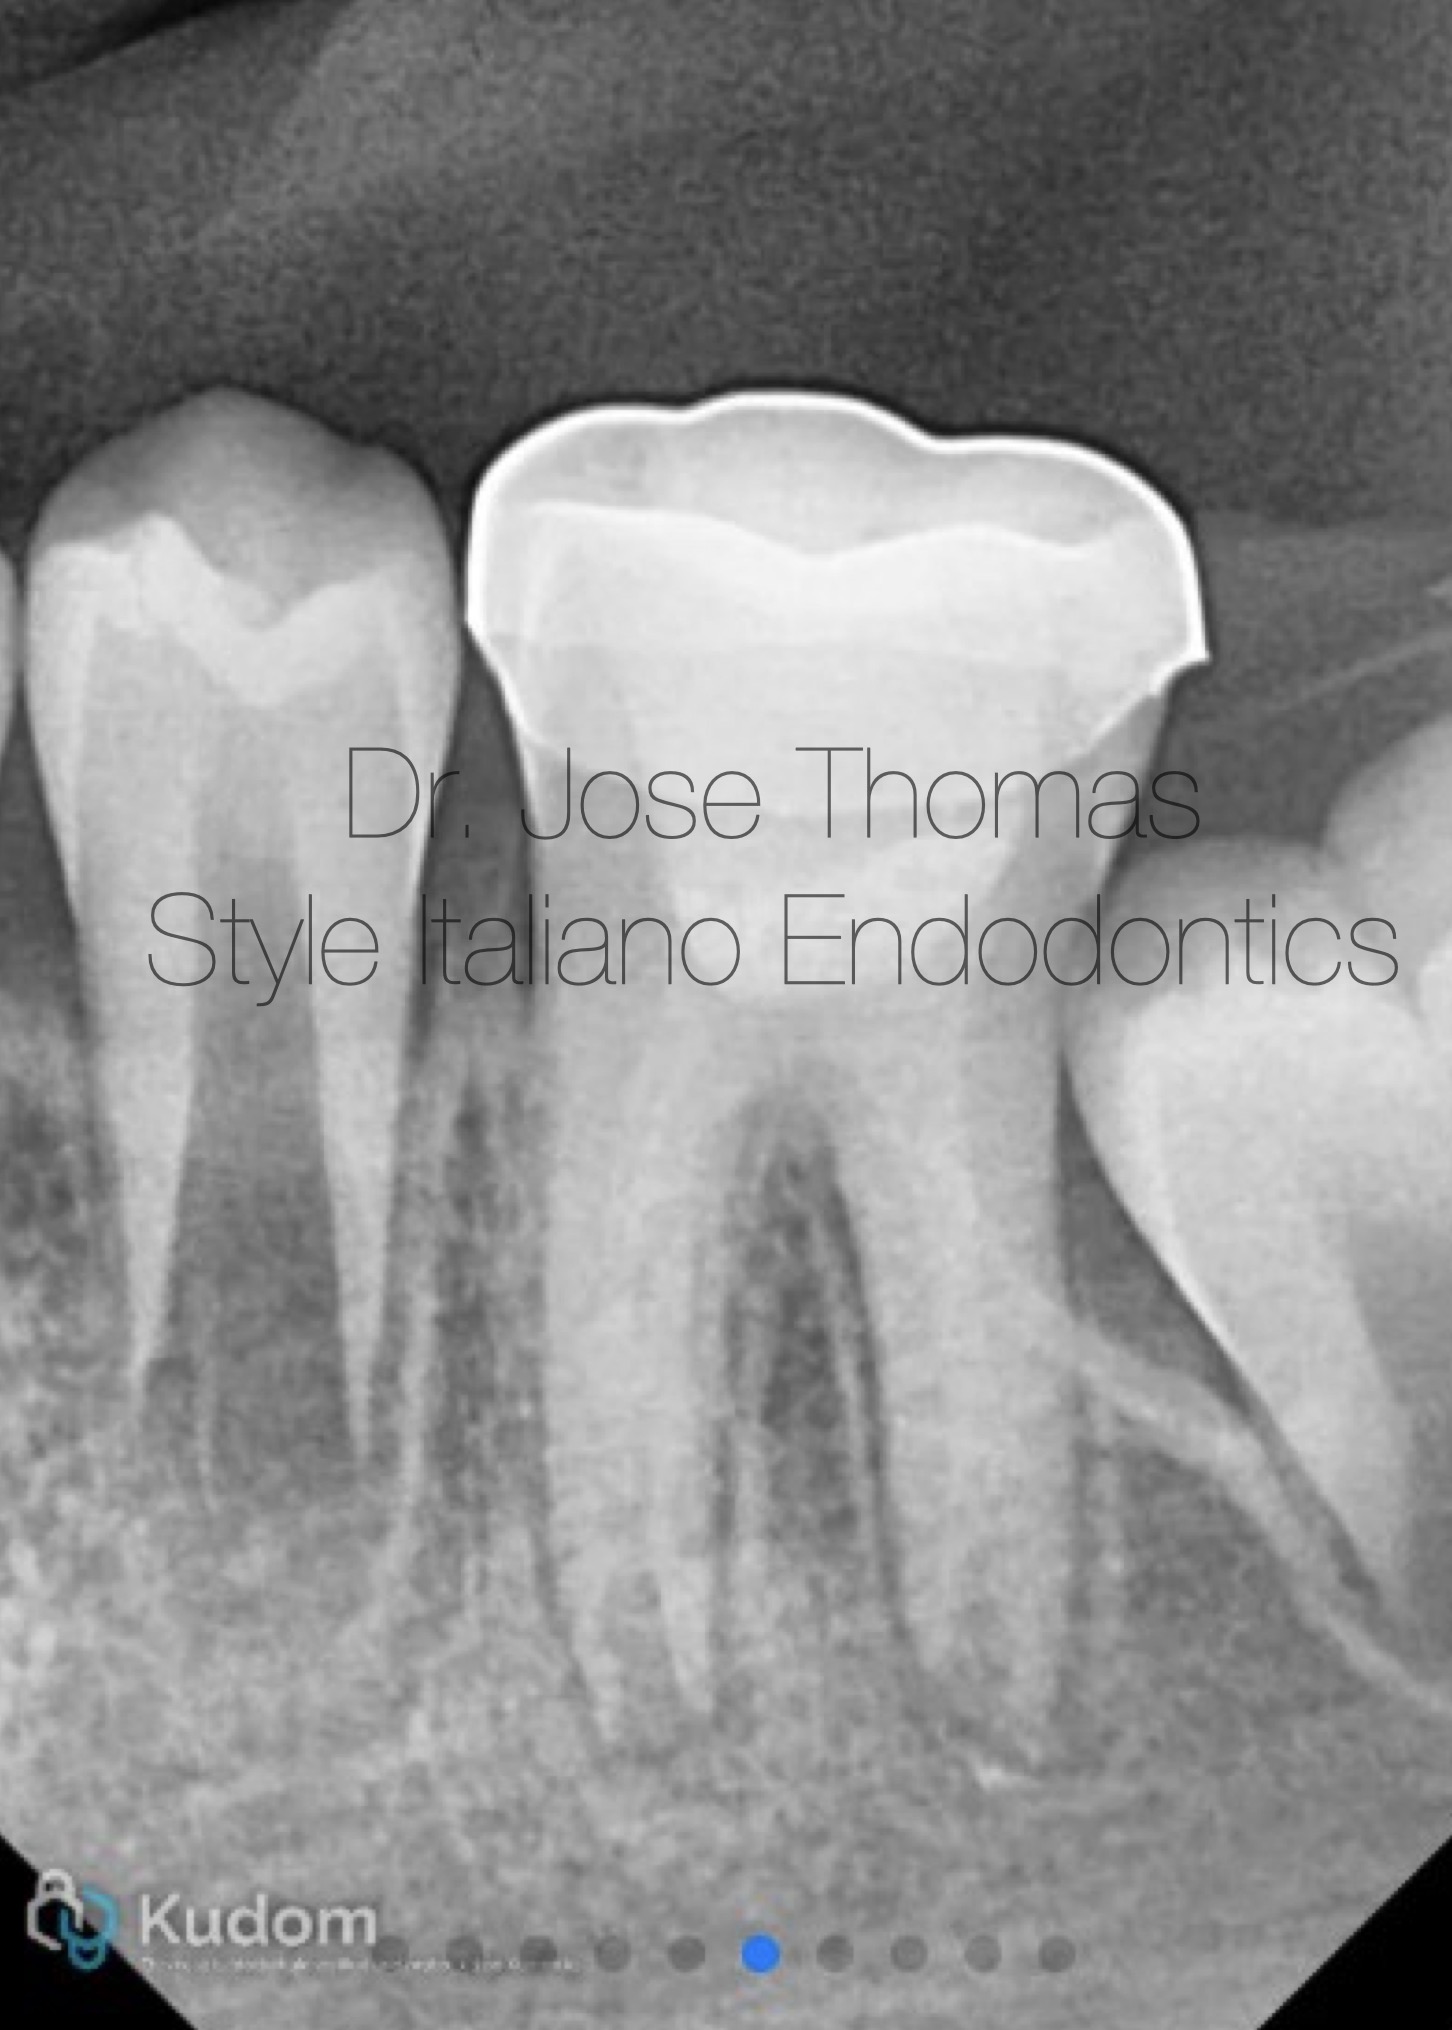

Fig. 4

The patient received a stainless-steel crown at a follow-up appointment one week later. Periodic follow-up was done till 30 months.

Xray after cementation of stainless steel crown